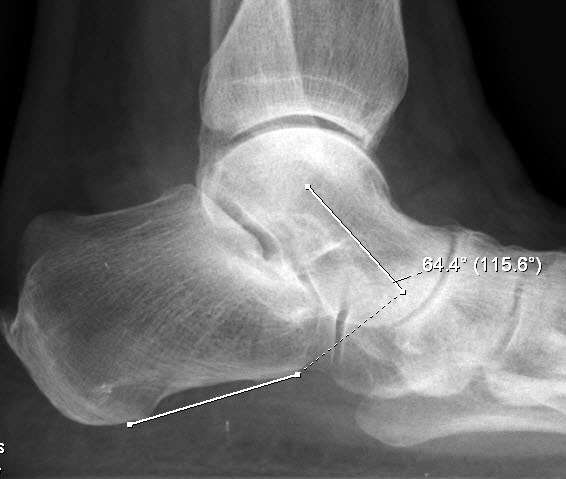

Talo-calcanearer Winkel (Abb. 6 e)

Auf der seitlichen, stehenden Aufnahme des Fußes wird ebenfalls der laterale Talo-Metatarsale I Winkel (Abb. 6 d) gemessen und so das kollabierte mediale Längsgewölbe dokumentiert. Auch hier gilt ein Talo-Metatarsale I Winkel von > 5° (nach plantar konvex) als pathologisch 21. Der Kollaps findet dabei meist im Talonaviculargelenk, seltener in der Naviculocuneiform-Gelenkreihe statt. Instabilität und Arthrose im 1. TMT sollten ausgeschlossen oder bei der Operationsplanung mit einbezogen werden. Weitere wichtige radiologische Messungen zur Beurteilung der Planovalgus-Statik und Progression der Deformität sind der laterale talo-calcaneare Winkel (Abb. 6 e) und der Abstand des Os cuneiforme-Unterrandes zum Untergrund (Abb. 6 f, Cuneiform height, 22. Eine anteriore Translation des Talus auf dem Kalkaneus findet man sowohl auf der ap, als auch auf der seitlichen Aufnahme des Fuβes mit Aufhebung der Cima-Linie.